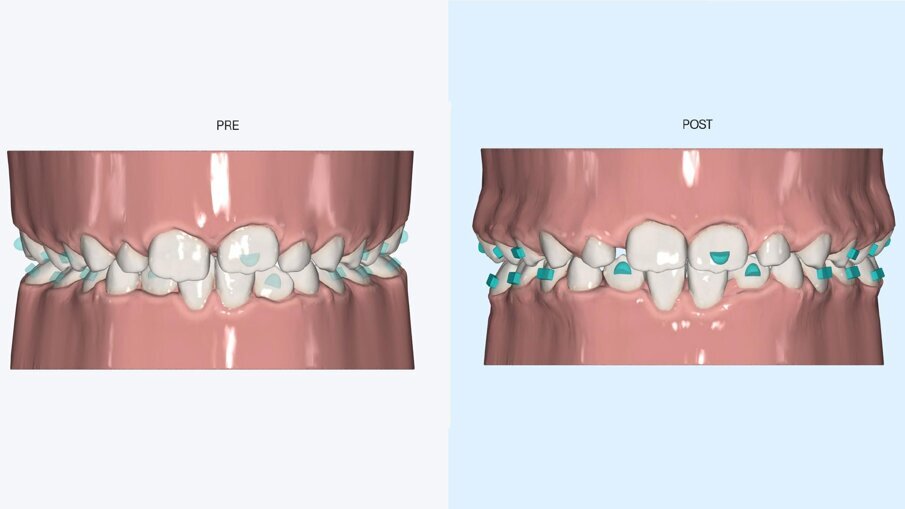

Fig. 3_Primo set up digitale.

Fig. 4_Programmazione dei movimenti di ottimizzazione trasversale.